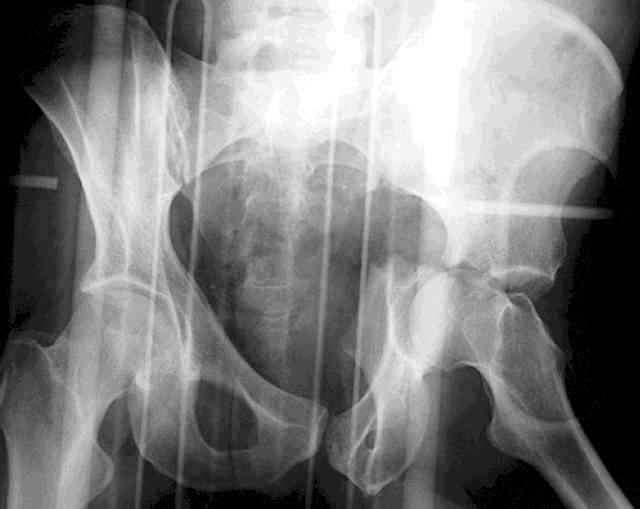

Understand that this is no simple fracture but in the same breath is very common and can be very routinely-simplistically treated without a variety of complicated and variable scenarios...keep it simple...turn him prone, clean him up, do a nice exposure, protect the nerve, remove the debris, save it and sort it out if you can, clean the fracture lines, manipulate and clamp the transverse, hold it how you choose (I'd recommend a percutaneously inserted 3.5mm antegrade medullary lag screw), remove the clamp, reduce the

small or impacted fragments to the head, reduce the wall, and support the wall and transverse with a balanced 3.5mm contoured reconstruction plate.